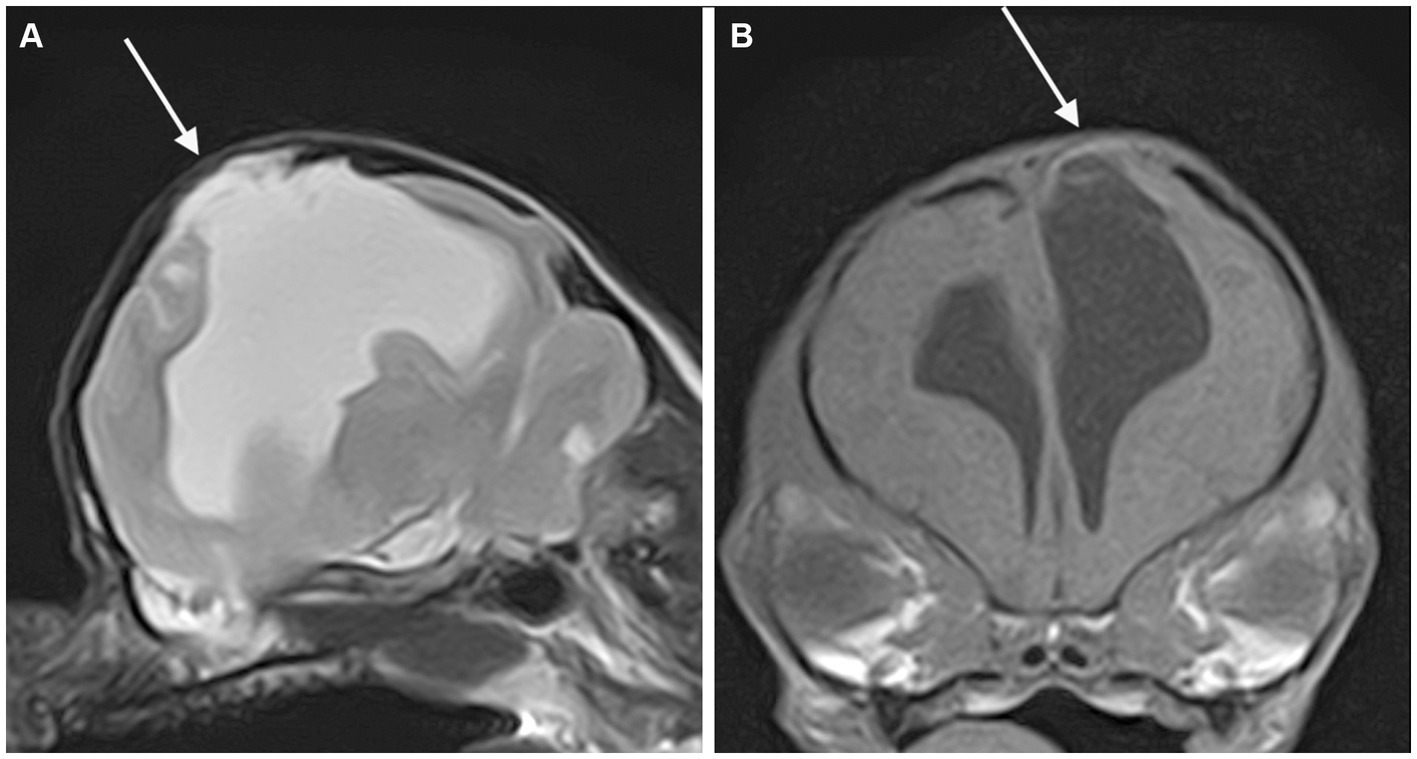

Figure 3

Dorsal (A) and transverse at the level of the inner ears (B) T1-weighted MR-images of the brain of a dog with an extensive unilateral cavity extending from the left lateral ventricle to the cortical surface. A severe mass effect leading to a right midline shift is present. The cranial vault over the porencephalic cyst is stretched and thinned (arrow).

All fourteen cases with fractures presented at least two further musculoskeletal changes and then were classified as presumed acquired traumatic forms (Figure 2). Thinning of the calvarium overlying the PC was seen in 3 cases (Figure 3). None of them presented further musculoskeletal abnormalities. Depression of the calvarium was seen in 13 cases, all but one of which were associated with fractures. Thirteen cases showed masticatory muscle changes, all but one of which were associated with fractures.

Concurrent abnormalities are listed in Table 3. Meningocele (MC) or meningoencephalocele (MEC) was seen in four cases, all located at the level of the parietal lobe (Figure 4).

Figure 4

Parasagittal T2-weighted (A) and transverse T1-weighted (B) MR-images of the brain of a dog showing a porencephalic cavity in the left parietal lobe and associated meningoencephalocele (arrow).